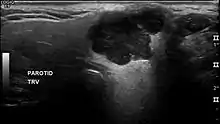

In terms of imaging studies, ultrasound can determine and characterize superficial parotid tumors. Certain types of salivary gland tumors have certain sonographic characteristics on ultrasound.[6] Ultrasound is also frequently used to guide FNA or core needle biopsy.

- ↑ Białek EJ, Jakubowski W, Karpińska G (September 2003). "Role of ultrasonography in diagnosis and differentiation of pleomorphic adenomas: work in progress". Archives of Otolaryngology–Head & Neck Surgery. 129 (9): 929–933. doi:10.1001/archotol.129.9.929. PMID 12975263.